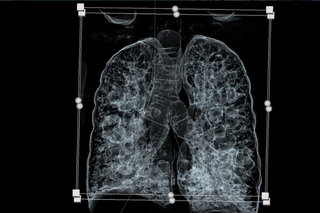

Stworzyliśmy druk 3D tchawicy i oskrzeli na podstawie obrazów tomografii komputerowej, który posłużył do opracowania techniki intubacji i wykonania operacji oskrzelowej. Zabieg nie byłby możliwy bez pomocy ECMO AV, ponieważ chory cierpiał również na ciężkie nadciśnienie płucne – informuje dr n. med. Maciej Urlik, kardiochirurg, specjalista transplantologii klinicznej ze Śląskiego Centrum Chorób Serca w Zabrzu.

Przygotowując się do operacji zespół zgromadził bogaty materiał obrazowy i histopatologiczny, który posłuży do napisania artykułu, który będzie przewodnikiem dla innych zespołów, ponieważ dotąd nie było opisu, jak tego typu zabieg wykonywać z punktu widzenia chirurgicznego i anestezjologicznego.